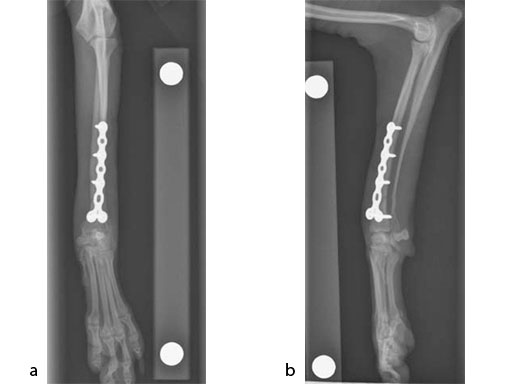

A 5-year-old female 3.5 kg dachshund with bilateral carpal hyperextension secondary to erosive polyarthroplathy (rheumatoid arthritis) (Fig 3, Fig 4) was treated bilaterally with a staged pancarpal arthrodesis with straight LCPs. The right carpus was operated first and healed in 10 weeks. The left carpus was operated 5 months after the initial surgery (Fig 5). Complete healing was noted 3 months postoperatively (Fig 6).

At the most recent follow-up 20 months postoperatively (first arthrodesis), the dog was comfortable and very active. The plates were selected based on the small bone size and the risk of secondary osteopenia. Locking screws are important to prevent screw loosening in patients with poor bone quality, especially in the case of pancarpal arthrodesis where high bending forces must be neutralized.